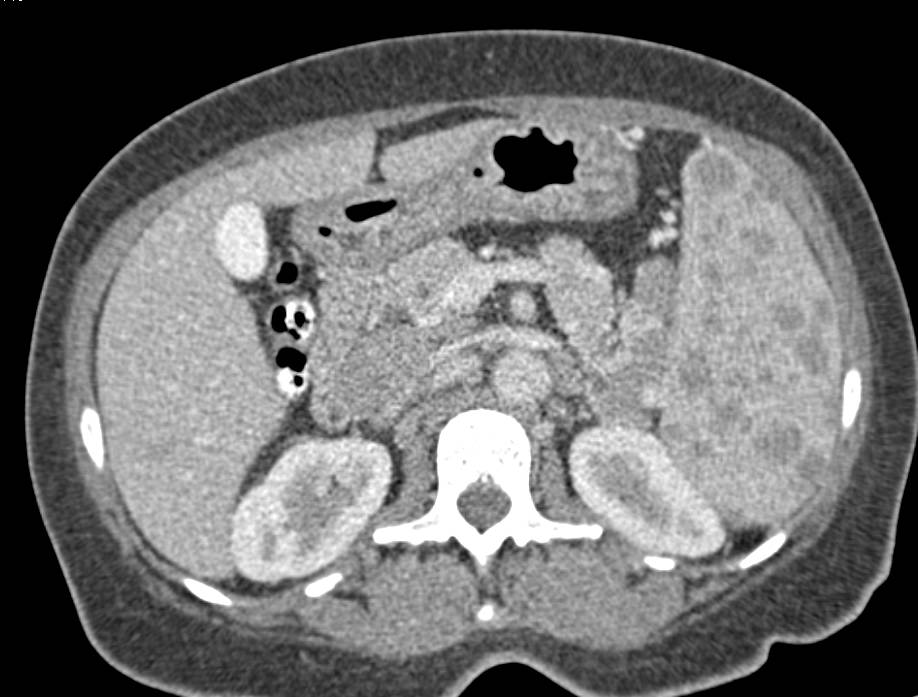

Lymphoma Involves the Liver and Spleen and Well as Extensive Nodes Especially Around the Pancreas